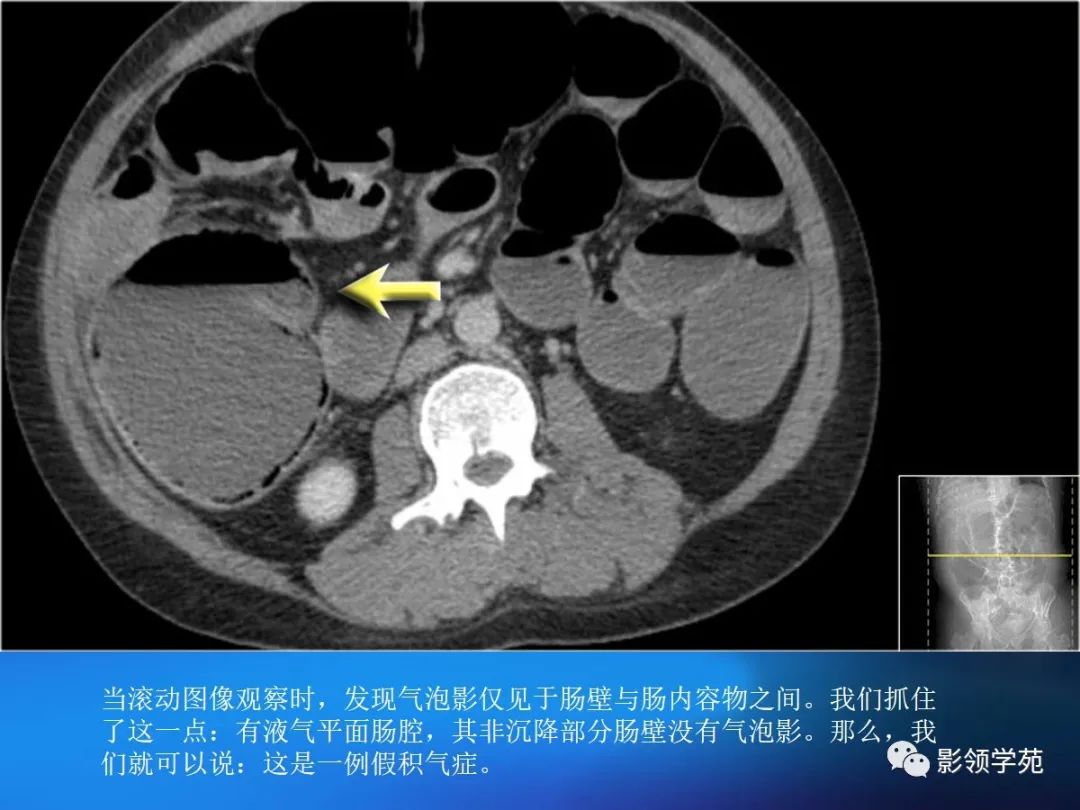

目前尚缺乏统一标准,一般认为,排除肠管充盈不佳或肠壁收缩时导致的假象后,当肠壁大于3mm是即考虑增厚。